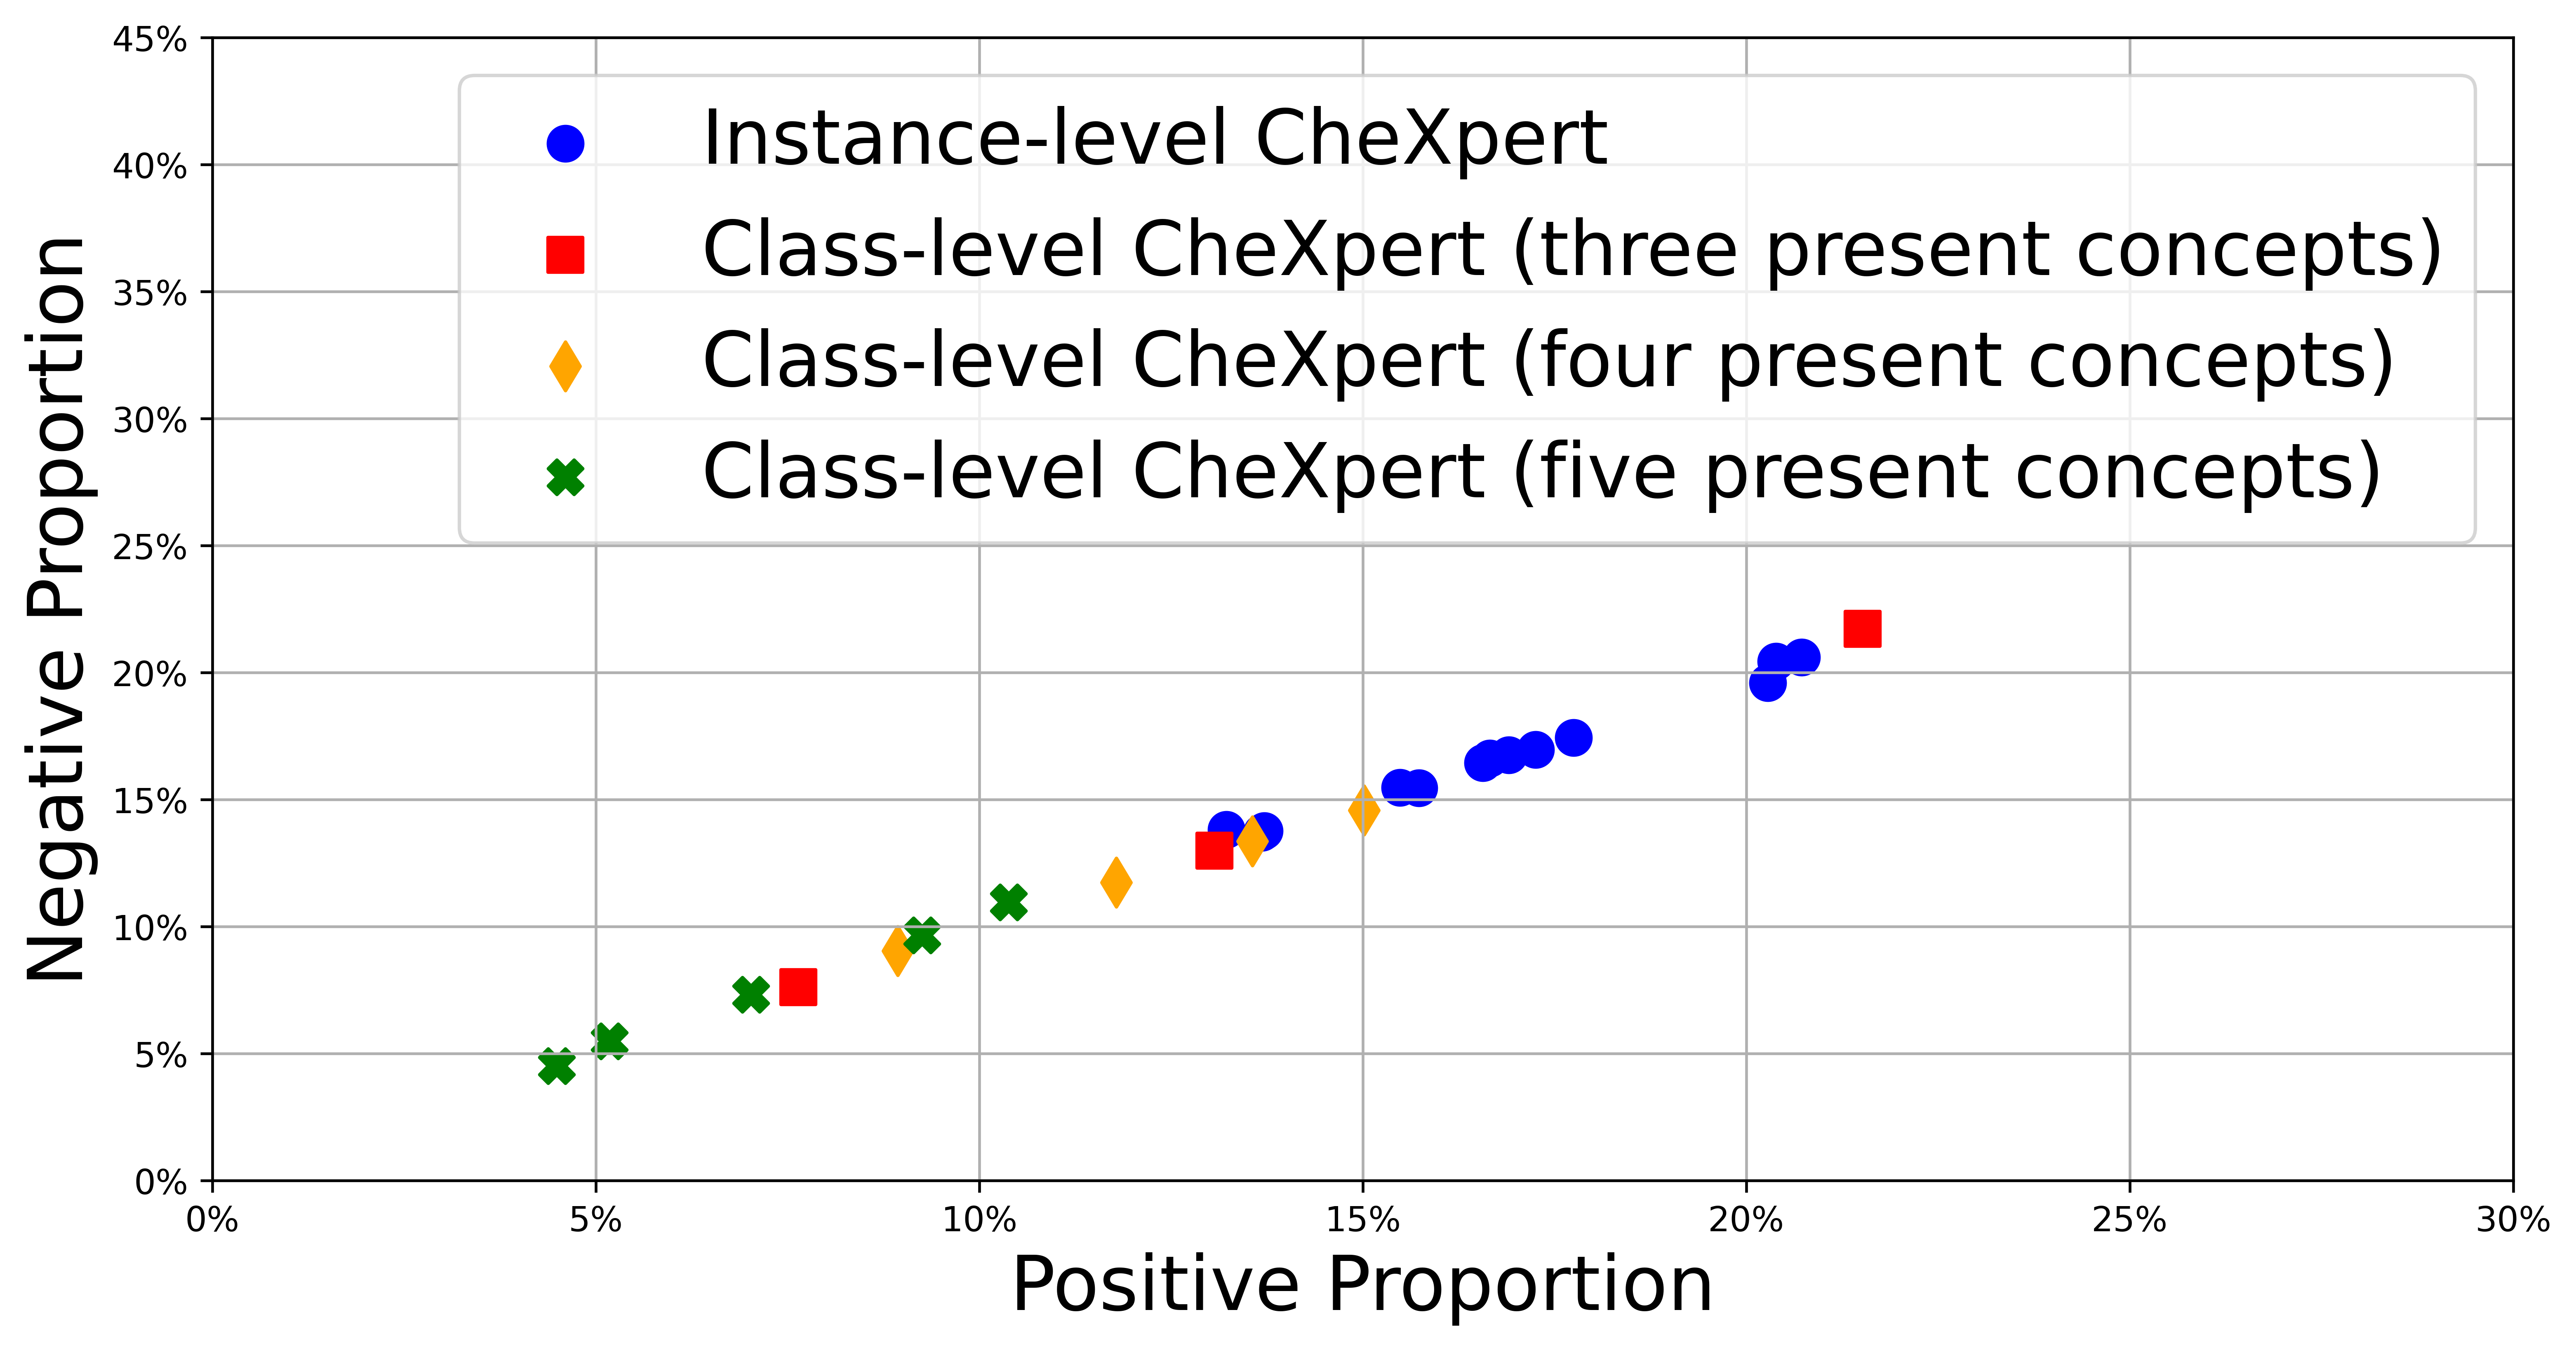

The proportion of relevance using our joint trained CheXpert models is shown in Figure 6. The maximum positive saliency is much lower than playing cards, topping out just over 20% and the concepts for instance-level CheXpert are not clustered but instead form a line. As discussed by Saporta et al. (2022), the most accurate concepts tend to be larger in size which could explain this. We are however more interested in the differences between instance-level CheXpert and class-level CheXpert. Instance-level CheXpert generally outperforms class-level CheXpert at mapping input features to concept segmentations. Most class-level concepts have a very little positive proportion of relevance located to the ground truth segmentations. We can therefore take away the concept annotations for instance-level CheXpert can confine models to learn semantic input features and further reinforces the need to avoid training CBMs on concepts that are only present together.